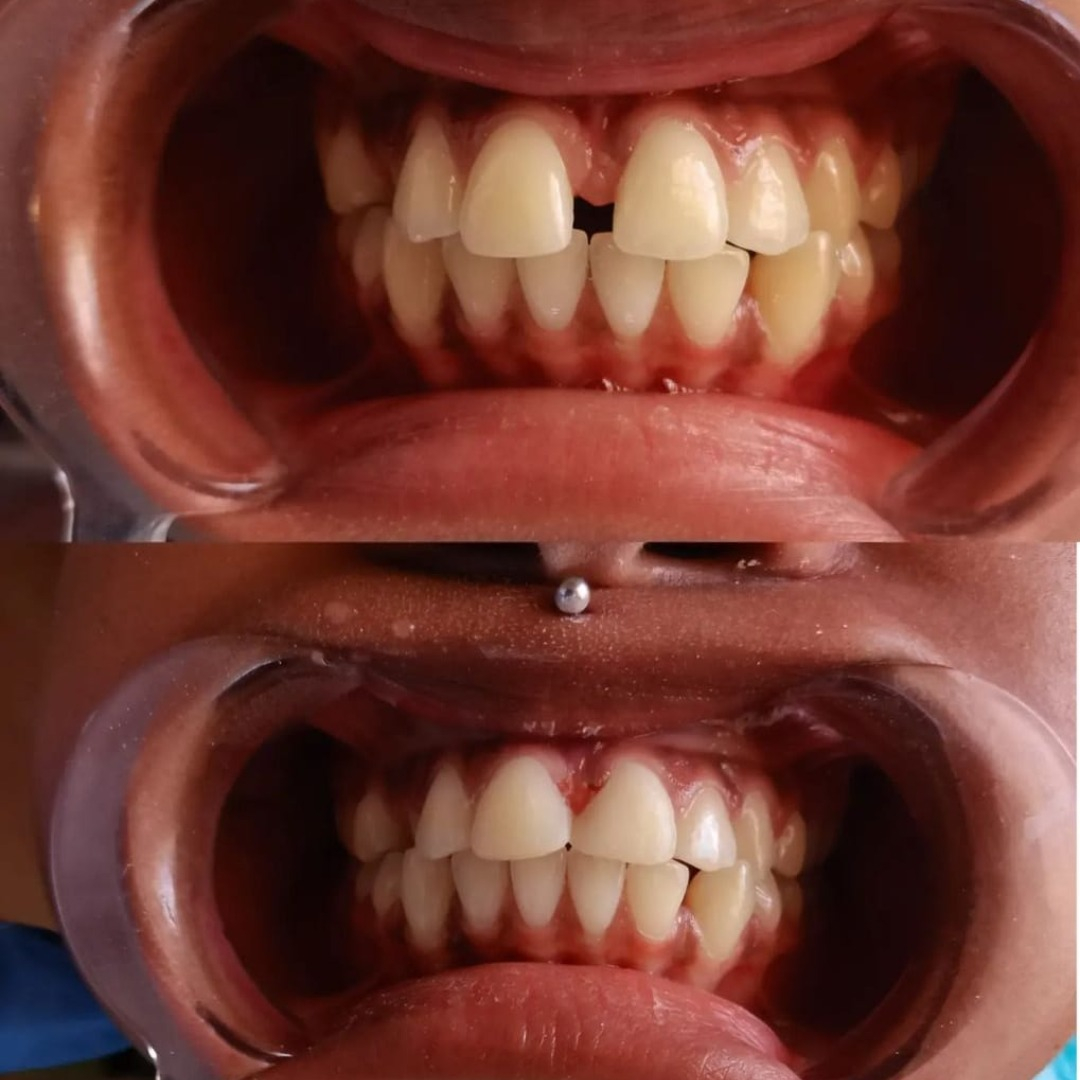

Our Latest Work